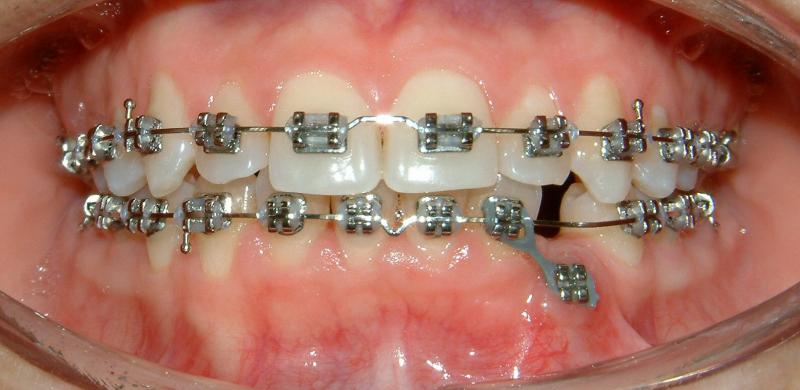

In the 3rd post-op visit (2 months after the surgery), the pulling is again activated. The progress of tooth movement can be seen, comparing the lengths of the elastic elements in Figs. 21 & 22. The newly-formed healthy gingiva can also be seen around the bracket that is attached to the crown of the lower left canine (Fig. 22).

Fig. 22 Third post-op visit, 2 months after surgical exposure; activated pulling (progress, complete healing)